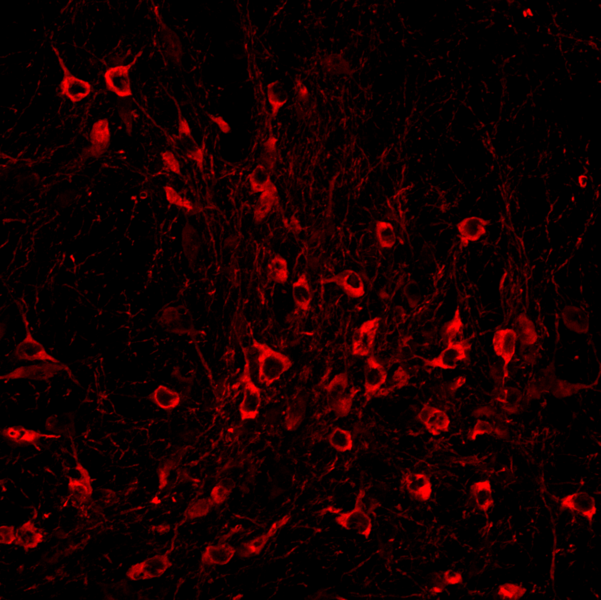

Dopamine-producing neurons in a brain region called the substantia nigra are known to be especially vulnerable to dying in Parkinson’s disease, leading to the severe motor difficulties experienced during the progression of the incurable, chronic neurodegenerative disorder. The field knows little about what puts specific cells at such dire risk, or what molecular mechanisms might help them resist the disease. In her research on Huntington’s disease, another incurable neurodegenerative disorder in which a specific neuron population in the striatum is especially vulnerable, Heiman has been able to use an innovative method her lab pioneered to discover genes whose expression promotes neuron survival, yielding potential new drug targets. The technique involves conducting an unbiased screen in which her lab knocks out each of the 22,000 genes expressed in the mouse brain one by one in neurons in disease model mice and healthy controls. The technique allows her to determine which genes, when missing, contribute to neuron death amid disease and therefore which genes are particularly needed for survival. The products of those genes can then be evaluated as drug targets. With the new Mathers award, Heiman plans to apply the method to study Parkinson’s disease.